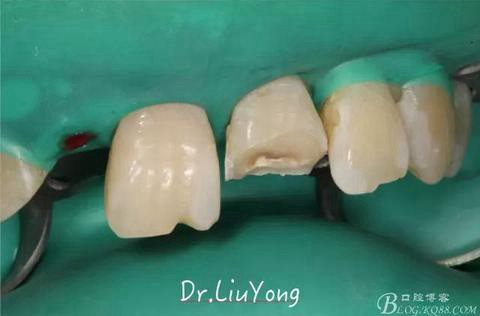

由于上前牙外傷后未及時(shí)行松牙固定,已拖延1月,因此先行松牙固定,嘗試保留。因A2冠根折,牙冠缺失,故行A1-B3松牙固定,選擇鄰面樹(shù)脂粘結(jié)固定,因?yàn)檠例l極易出血,因此選擇橡皮障下用流體樹(shù)脂進(jìn)行松牙固定。同時(shí)A2B1根管治療。